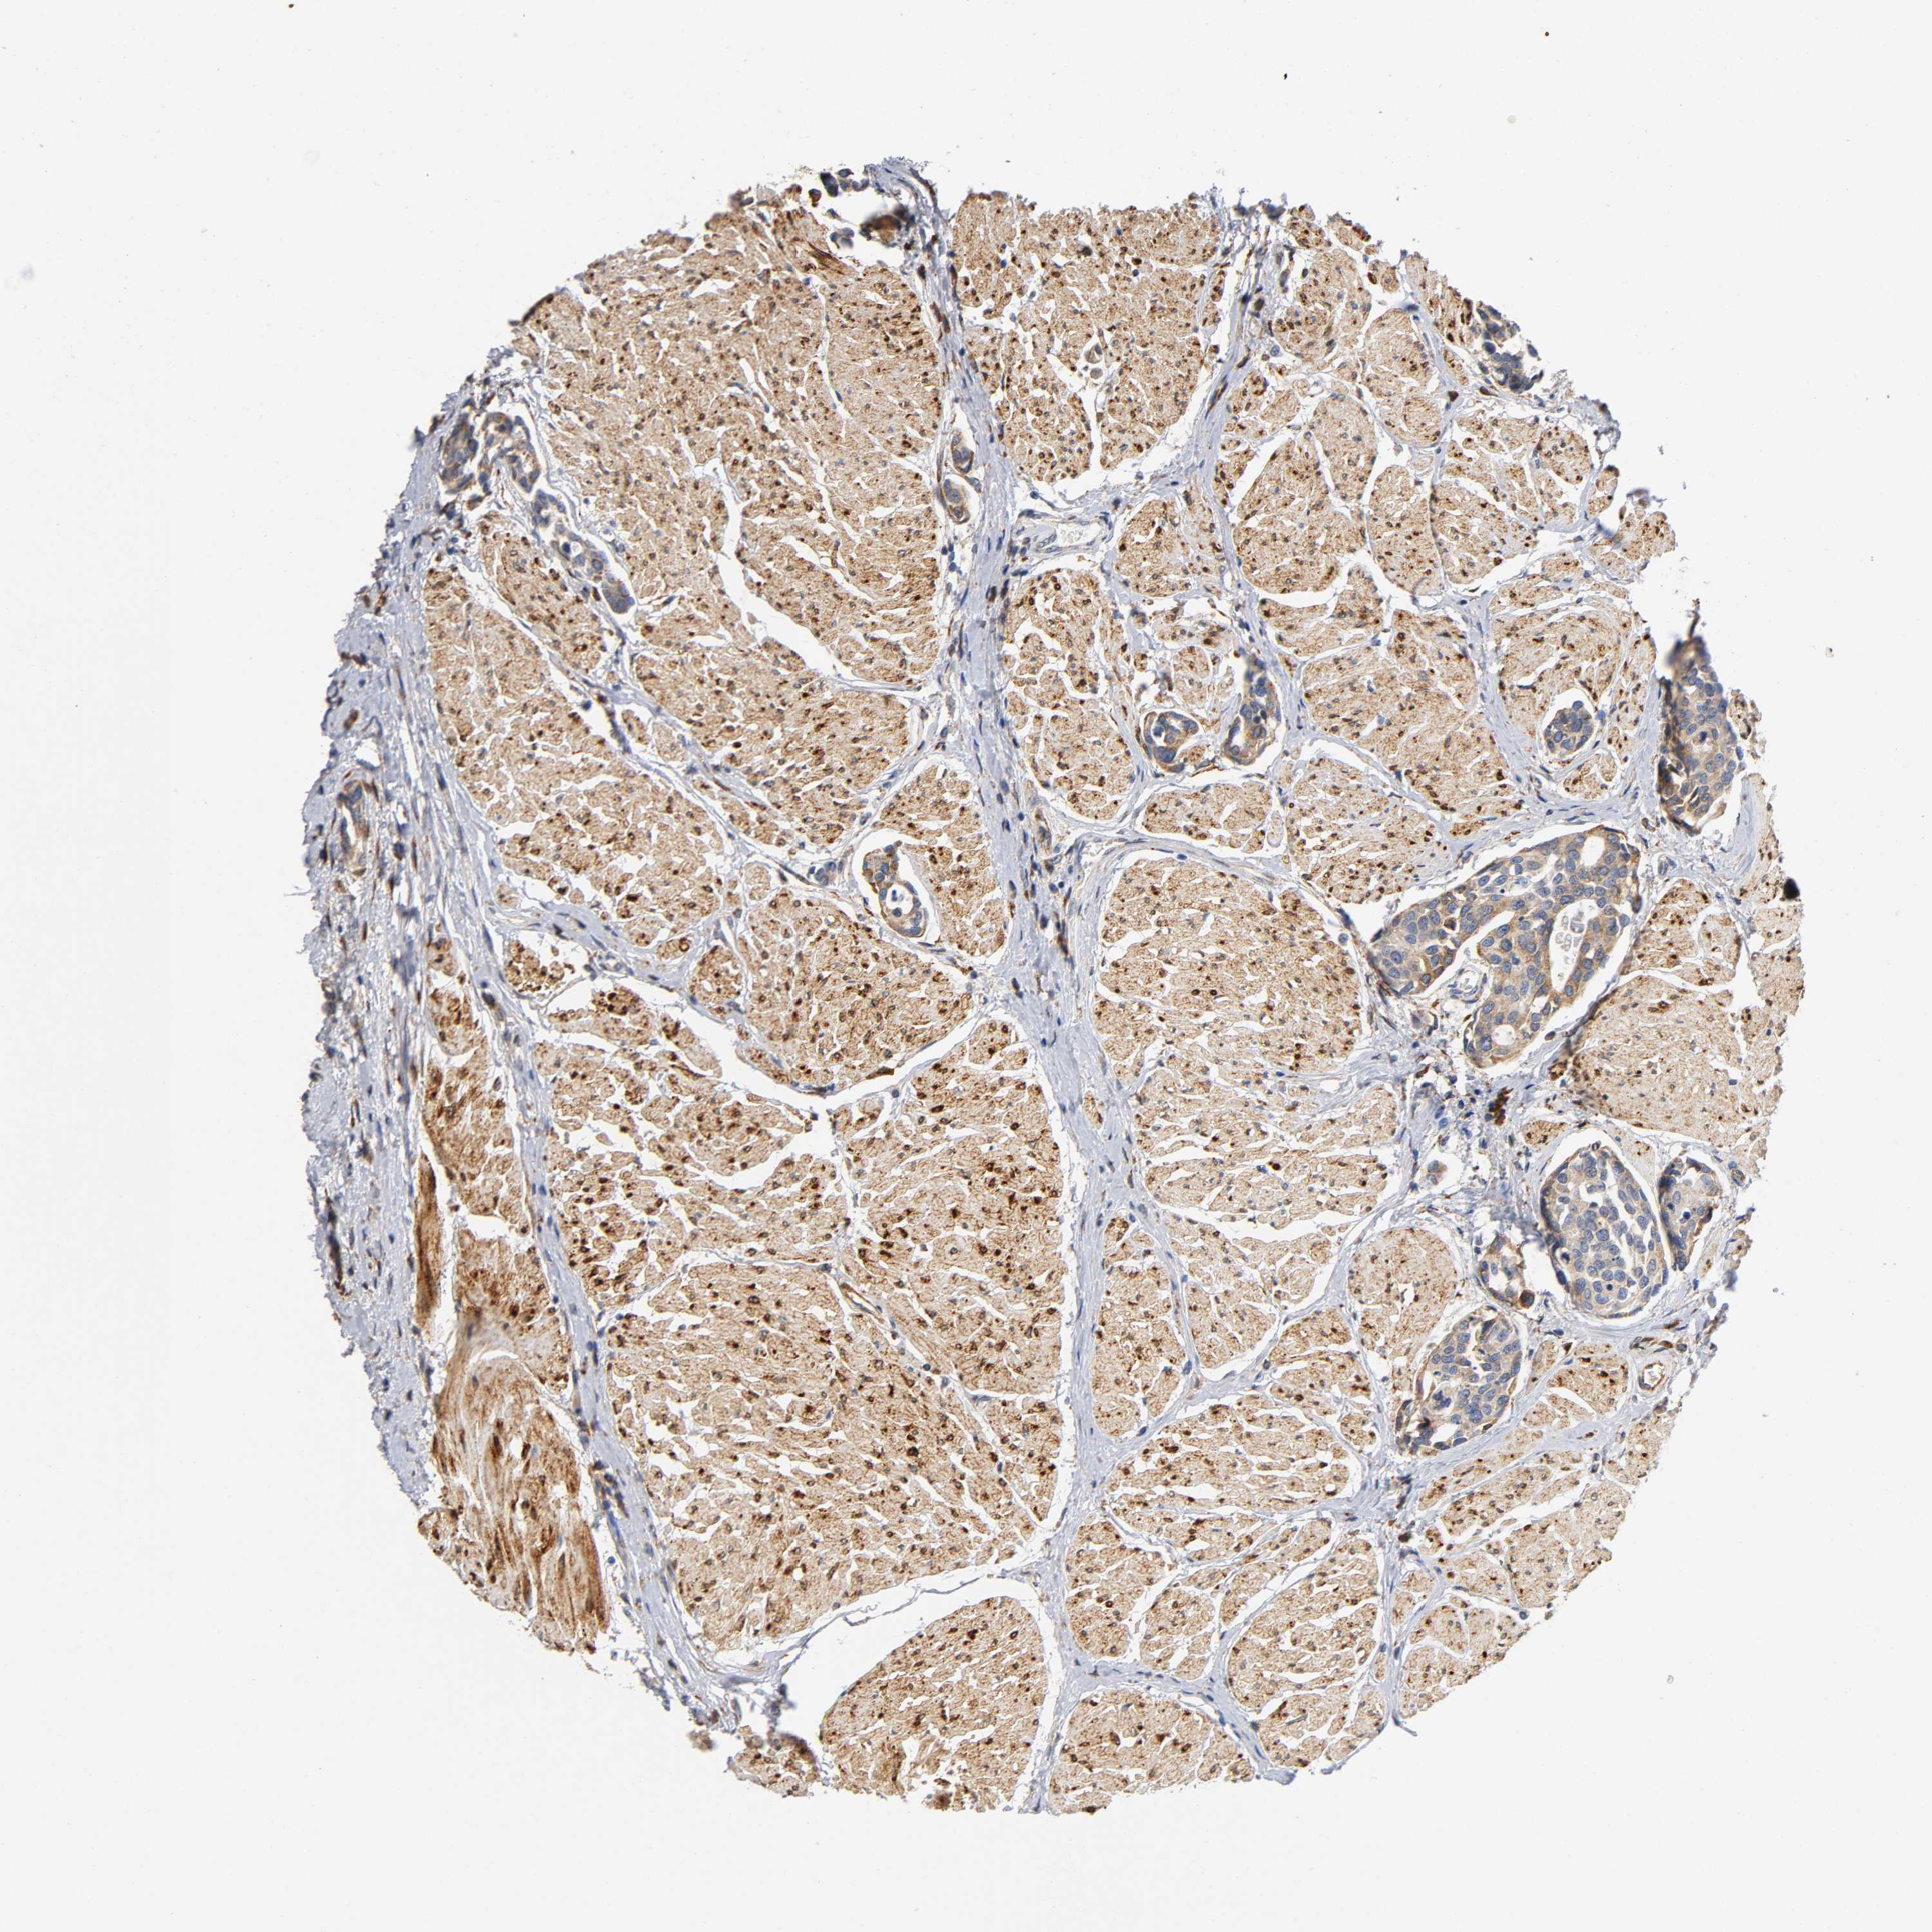

UROTHELIAL CANCER - Protein expressioni

A mouse-over function shows sample information and annotation data. Click on an image to view it in a full screen mode. Samples can be filtered based on level of antibody staining by selecting one or several of the following categories: high, medium, low and not detected. The assay and annotation is described here.

Antibody stainingi

Antibody staining in the annotated cell types in the current human tissue is reported as not detected, low, medium, or high, based on conventional immunohistochemistry profiling in selected tissues. This score is based on the combination of the staining intensity and fraction of stained cells.

Each image is clickable and will lead to virtual microscopy that enables deeper exploration of all samples and also displays staining intensity scores, fraction scores and subcellular localization as well as patient and tissue information for each sample.

Antibody HPA047368

Antibody CAB004577

Staining

High

Medium

Low

Not detected

Intensity

Strong

Moderate

Weak

Negative

Quantity

>75%

75%-25%

<25%

None

Location

Nuclear

Cytoplasmic/membranous

Cytoplasmic/membranous,nuclear

Urothelial carcinoma, High grade